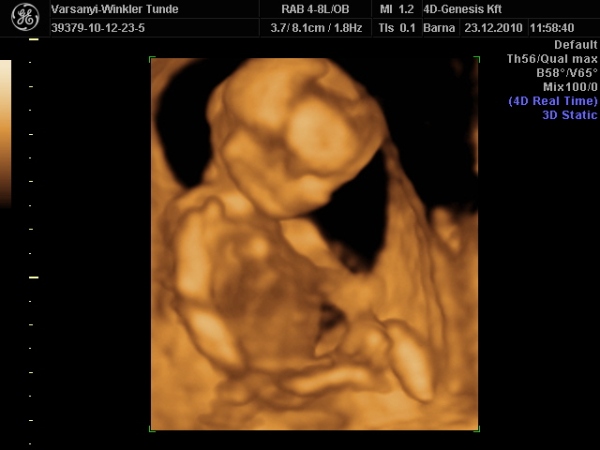

Bár tegnap a dokor bácsi azt mondta, hogy azért lassan vissza kellene vennem a lendületből, mert nem lesz jó vége. Manócska jól van, de tegnap nem tudtuk megnézni. Hasi uh-val próbálkozott, de pont úgy fordult, hogy csak a nagy kobakját láttuk

Gondolta, ha arra van a feje, akkor lentről lehet látni valamit a neméből.

Be is terpesztett rendesen, mint egy kis utcalány

Természetesen lánynak is látszott, bár azt mondta, hogy még ne éljük bele magunkat. A férjem le is tört egy kicsit, de nem vallotta volna be.Holnap reggel megyek AFP-re.